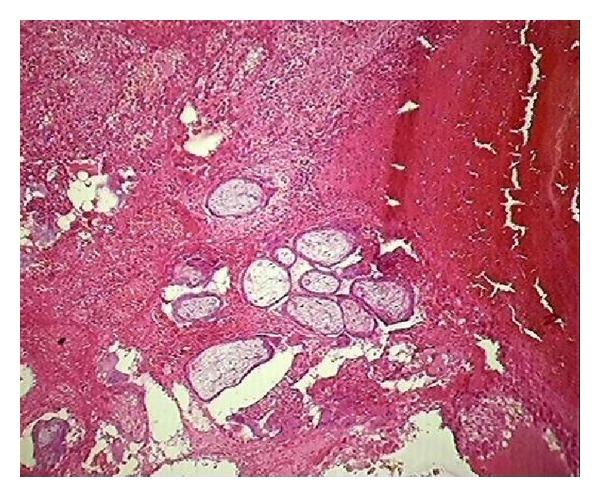

Hysterectomy, the most common gynecological surgery, provides a definitive cure to various diseases like DUB (dysfunctional uterine bleeding), leiomyoma, adenomyosis, chronic pelvic pain, prolapse, and malignancy. However, with advent of effective medical and conservative treatment modalities for nononcological causes it is now posing question mark on justification of hysterectomy. Therefore, an audit is required to assess the correlation between preoperative diagnosis and histopathological examination of specimen for justification of the procedure. In this study over period of one year (April 2013 to March 2014) 373 hysterectomies specimens were received in the department of pathology for nononcological causes. The age of patients ranged from 22 to 85 years with mean 45 ± 9.2 years. All cases were divided into five categories on the basis of age and audit was done. In this study the most common finding was leiomyoma (43.7%) followed by adenomyosis (19.3%). Almost 50% of hysterectomies causes were justified as preoperative diagnosis matched with histopathology. Cohen kappa statistics were used to measure agreement between preoperative and postoperative histopathological diagnosis which was found to be fair with κ value being 0.36. This study highlights that regular audit of surgeries can help improve quality of health care services and provide safe conservative option to patients.

子宫切除术是最常见的妇科手术,可有效治愈多种疾病,如功能失调性子宫出血(DUB)、平滑肌瘤、子宫腺肌病、慢性盆腔疼痛、子宫脱垂和恶性肿瘤。然而,随着针对非肿瘤性病因的有效药物和保守治疗方式的出现,子宫切除术的合理性如今受到了质疑。因此,需要进行一项审计,以评估术前诊断与标本组织病理学检查之间的相关性,从而证明该手术的合理性。在本研究中,在一年时间(2013年4月至2014年3月)内,病理科接收了373例因非肿瘤性病因进行子宫切除的标本。患者年龄在22岁至85岁之间,平均年龄为45±9.2岁。所有病例根据年龄分为五类并进行了审计。在本研究中,最常见的发现是平滑肌瘤(43.7%),其次是子宫腺肌病(19.3%)。几乎50%的子宫切除病因被证明是合理的,因为术前诊断与组织病理学结果相符。采用科恩kappa统计量来衡量术前和术后组织病理学诊断之间的一致性,发现一致性一般,κ值为0.36。本研究强调,定期对手术进行审计有助于提高医疗服务质量,并为患者提供安全的保守选择。